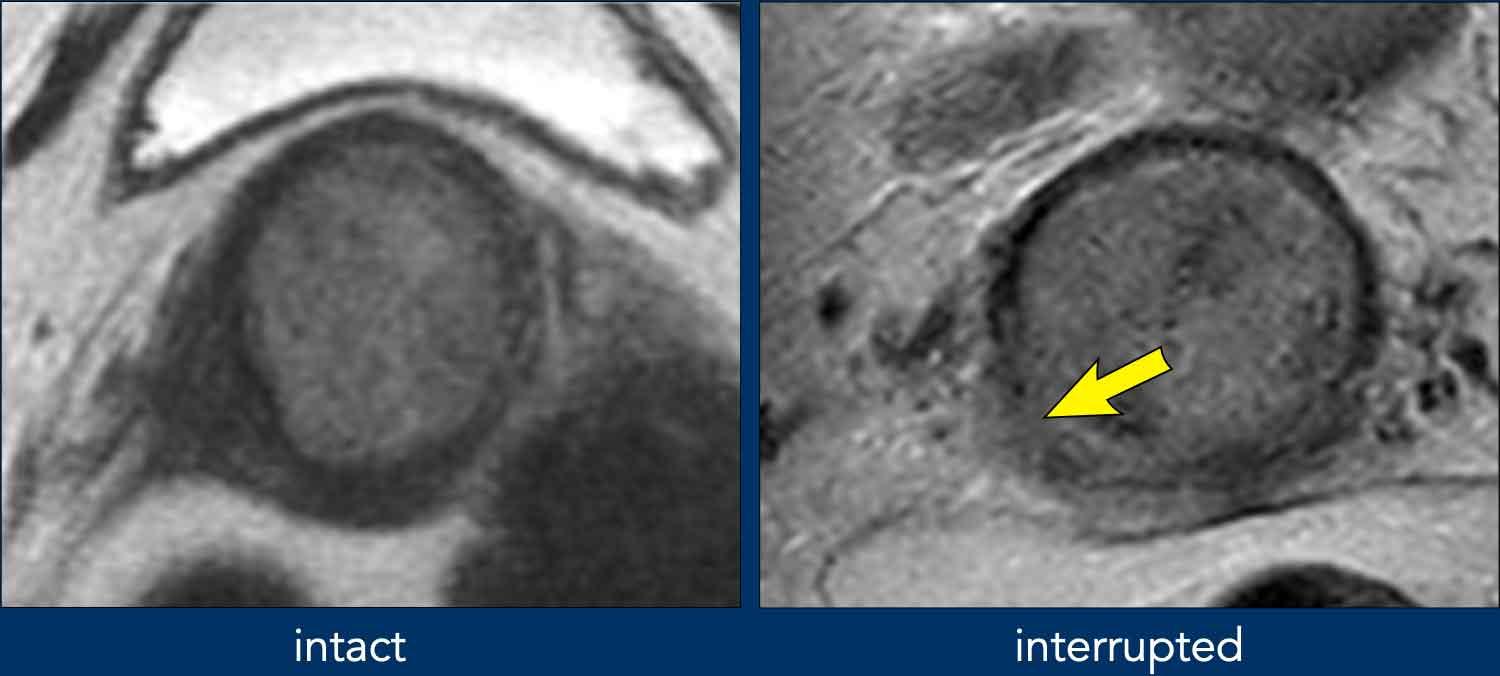

Xâm lấn cạnh cổ tử cung

Khi vòng mô đệm giảm tín hiệu của cổ tử cung còn nguyên vẹn (hình bên trái), MRI có thể dự đoán sự vắng mặt của xâm lấn cạnh cổ tử cung với giá trị tiên đoán âm cao hơn 90%.

Sự gián đoạn của vòng mô đệm giảm tín hiệu của cổ tử cung (hình bên phải) và tín hiệu khối u hoặc khối mô mềm lan rộng vào vùng cạnh cổ tử cung là các dấu hiệu gợi ý xâm lấn cạnh cổ tử cung (giai đoạn FIGO IIB).

Bẫy chẩn đoán

– Giãn rộng so với xâm lấn

Ví dụ này cho thấy một khối u lớn làm giãn rộng cổ tử cung.

Lưu ý rằng không có xâm lấn thực sự vào vùng cạnh cổ tử cung vì vòng mô đệm giảm tín hiệu của cổ tử cung hoàn toàn còn nguyên vẹn như được chỉ ra bởi các đầu mũi tên.